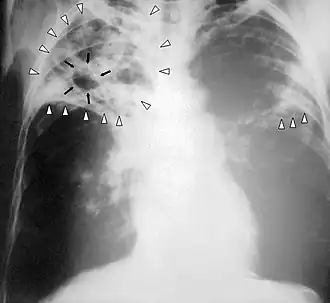

Tuberculosis-x-ray

• Chest X-Ray - pericardial calcification (common but not specific), pleural effusions are common findings.[11]